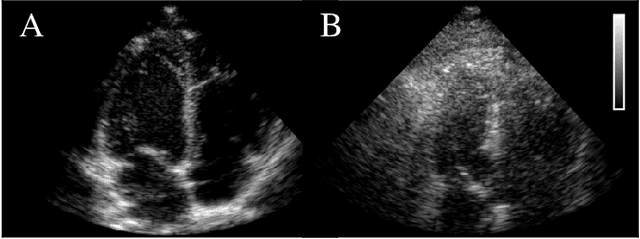

Abstract:Echocardiography has been a prominent tool for the diagnosis of cardiac disease. However, these diagnoses can be heavily impeded by poor image quality. Acoustic clutter emerges due to multipath reflections imposed by layers of skin, subcutaneous fat, and intercostal muscle between the transducer and heart. As a result, haze and other noise artifacts pose a real challenge to cardiac ultrasound imaging. In many cases, especially with difficult-to-image patients such as patients with obesity, a diagnosis from B-Mode ultrasound imaging is effectively rendered unusable, forcing sonographers to resort to contrast-enhanced ultrasound examinations or refer patients to other imaging modalities. Tissue harmonic imaging has been a popular approach to combat haze, but in severe cases is still heavily impacted by haze. Alternatively, denoising algorithms are typically unable to remove highly structured and correlated noise, such as haze. It remains a challenge to accurately describe the statistical properties of structured haze, and develop an inference method to subsequently remove it. Diffusion models have emerged as powerful generative models and have shown their effectiveness in a variety of inverse problems. In this work, we present a joint posterior sampling framework that combines two separate diffusion models to model the distribution of both clean ultrasound and haze in an unsupervised manner. Furthermore, we demonstrate techniques for effectively training diffusion models on radio-frequency ultrasound data and highlight the advantages over image data. Experiments on both \emph{in-vitro} and \emph{in-vivo} cardiac datasets show that the proposed dehazing method effectively removes haze while preserving signals from weakly reflected tissue.